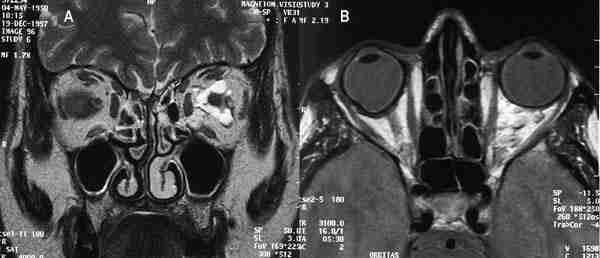

Más del 90% de los RTB muestran calcificación en tomografía computada (TC), generalmente en la porción posterior del globo (4). Su aspecto es variable, única o múltiple, finas o gruesas. Si el tumor es pequeño la calcificación puede ser difícil de identificar (5). La TC permite hacer cortes seriados de 1,5 a 3 mm de espesor o estudiar un volumen orbitario mediante técnica helicoidal. En el estudio con contraste intravenoso el realce tumoral es mínimo o moderado, no obstante puede ayudar a identificar enfermedad retrobulbar e intracraneal aunque para ello es más sensible la resonancia magnética (figuras 2a y 2b).

53-02.jpg (9588 bytes)

Figuras 2a, b y c. Retinoblastomas bilaterales calcificados. Imágenes axiales mediante TC (a, b) y secuencia potenciada en T2 de RM. El calcio se define mejor en el estudio de TC.

La resonancia magnética (RM) muestra menor sensibilidad en la detección de calcio que la US o la TC, sin embargo supera a estas dos técnicas en la valoración de extensión local, diseminación al SNC y en el diagnóstico diferencial con entidades que simulan al RTB (1) (figura 2c). El tumor aparece iso o levemente hiperintenso respecto al vítreo en secuencia eco de espín potenciada en T1 (SET1) en relación a hemorragia intratumoral y al depósito de sustancias paramagnéticas asociadas a calcificaciones tumorales (6) (figura 3). En secuencia eco de espín potenciada en T2 (SET2) la señal del tumor es hipointensa respecto al vítreo. El grado de extensión local se valora tras la administración de gadolinio intravenoso mediante secuencias SET1 con saturación de la grasa. Aunque el realce tumoral es variable, siempre ha de realizarse estudio con contraste ya que ayuda a identificar enfermedad retrobulbar (4).

53-03.jpg (12263 bytes)

Figura 3. Secuencia axial potenciada en T2 de retinoblastoma bilateral con hemorragia vítrea asociada en el lado izquierdo.